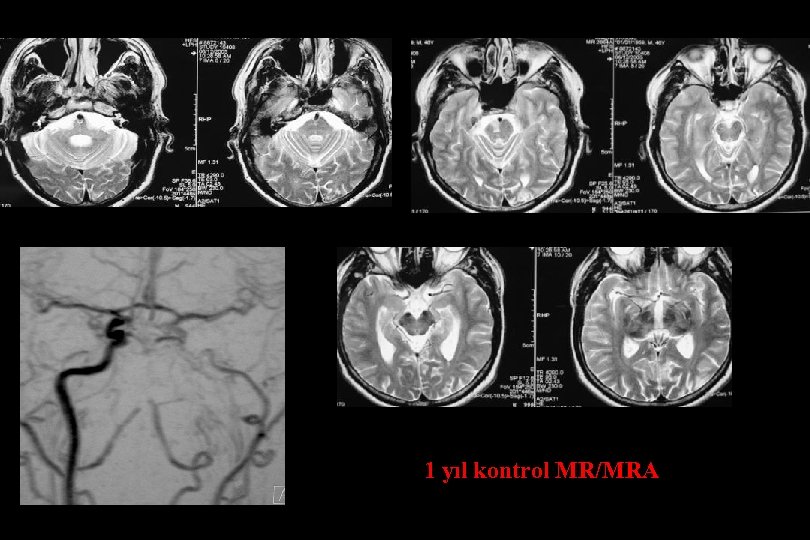

3 yıl kontrol

2. Yıl kontrol

11 yıl kontrol MR/MRA

1 yıl kontrol

6 ay kontrol

1. Yıl kontrol

1 yıl kontrol PTA Sonrası